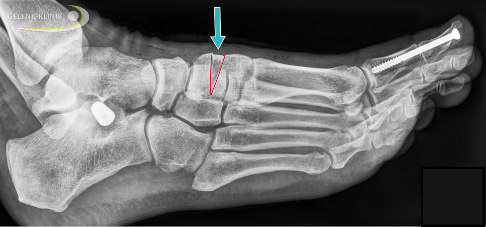

Röntgenbild nach einer Cotton-Osteotomie. Der Pfeil zeigt auf den knöchernen Keil (hier Fremdmaterial durch Spenderknochen). Weiterhin sichtbar im Bild sind eine Versteifung des Großzehenendgelenkes mittels Schraube (rechts) und eine Sinus-tarsi-Spreizprothese zwischen Sprungbein und Fersenbein (links). © Gelenk-Klinik

Bei der Cotton-Osteotomie handelt es sich um ein operatives Verfahren zur Behandlung des erworbenen Knick-Senkfußes. Sie zielt darauf, das Fußlängsgewölbe wieder aufzurichten. Im Gegensatz zu rückfußnahen gewölbeaufrichtenden Techniken setzt die Cotton-Osteotomie am Mittelfuß an.

Durch Implantation eines Keils in das mediale, am Fußinnenrand liegende Keilbein (Os cuneiforme I) wird der erste Strahl (also der Bereich der Großzehe) abgesenkt und gleichzeitig das Gewölbe angehoben. In der Folge stabilisiert sich das Fußlängsgewölbe und der Fuß rollt beim Gehen wieder über den ersten Strahl ab. Ohne diese Korrektur käme es zu einer vermehrten Belastung des lateralen Fußrandes, was für den Patienten ungünstig wäre.